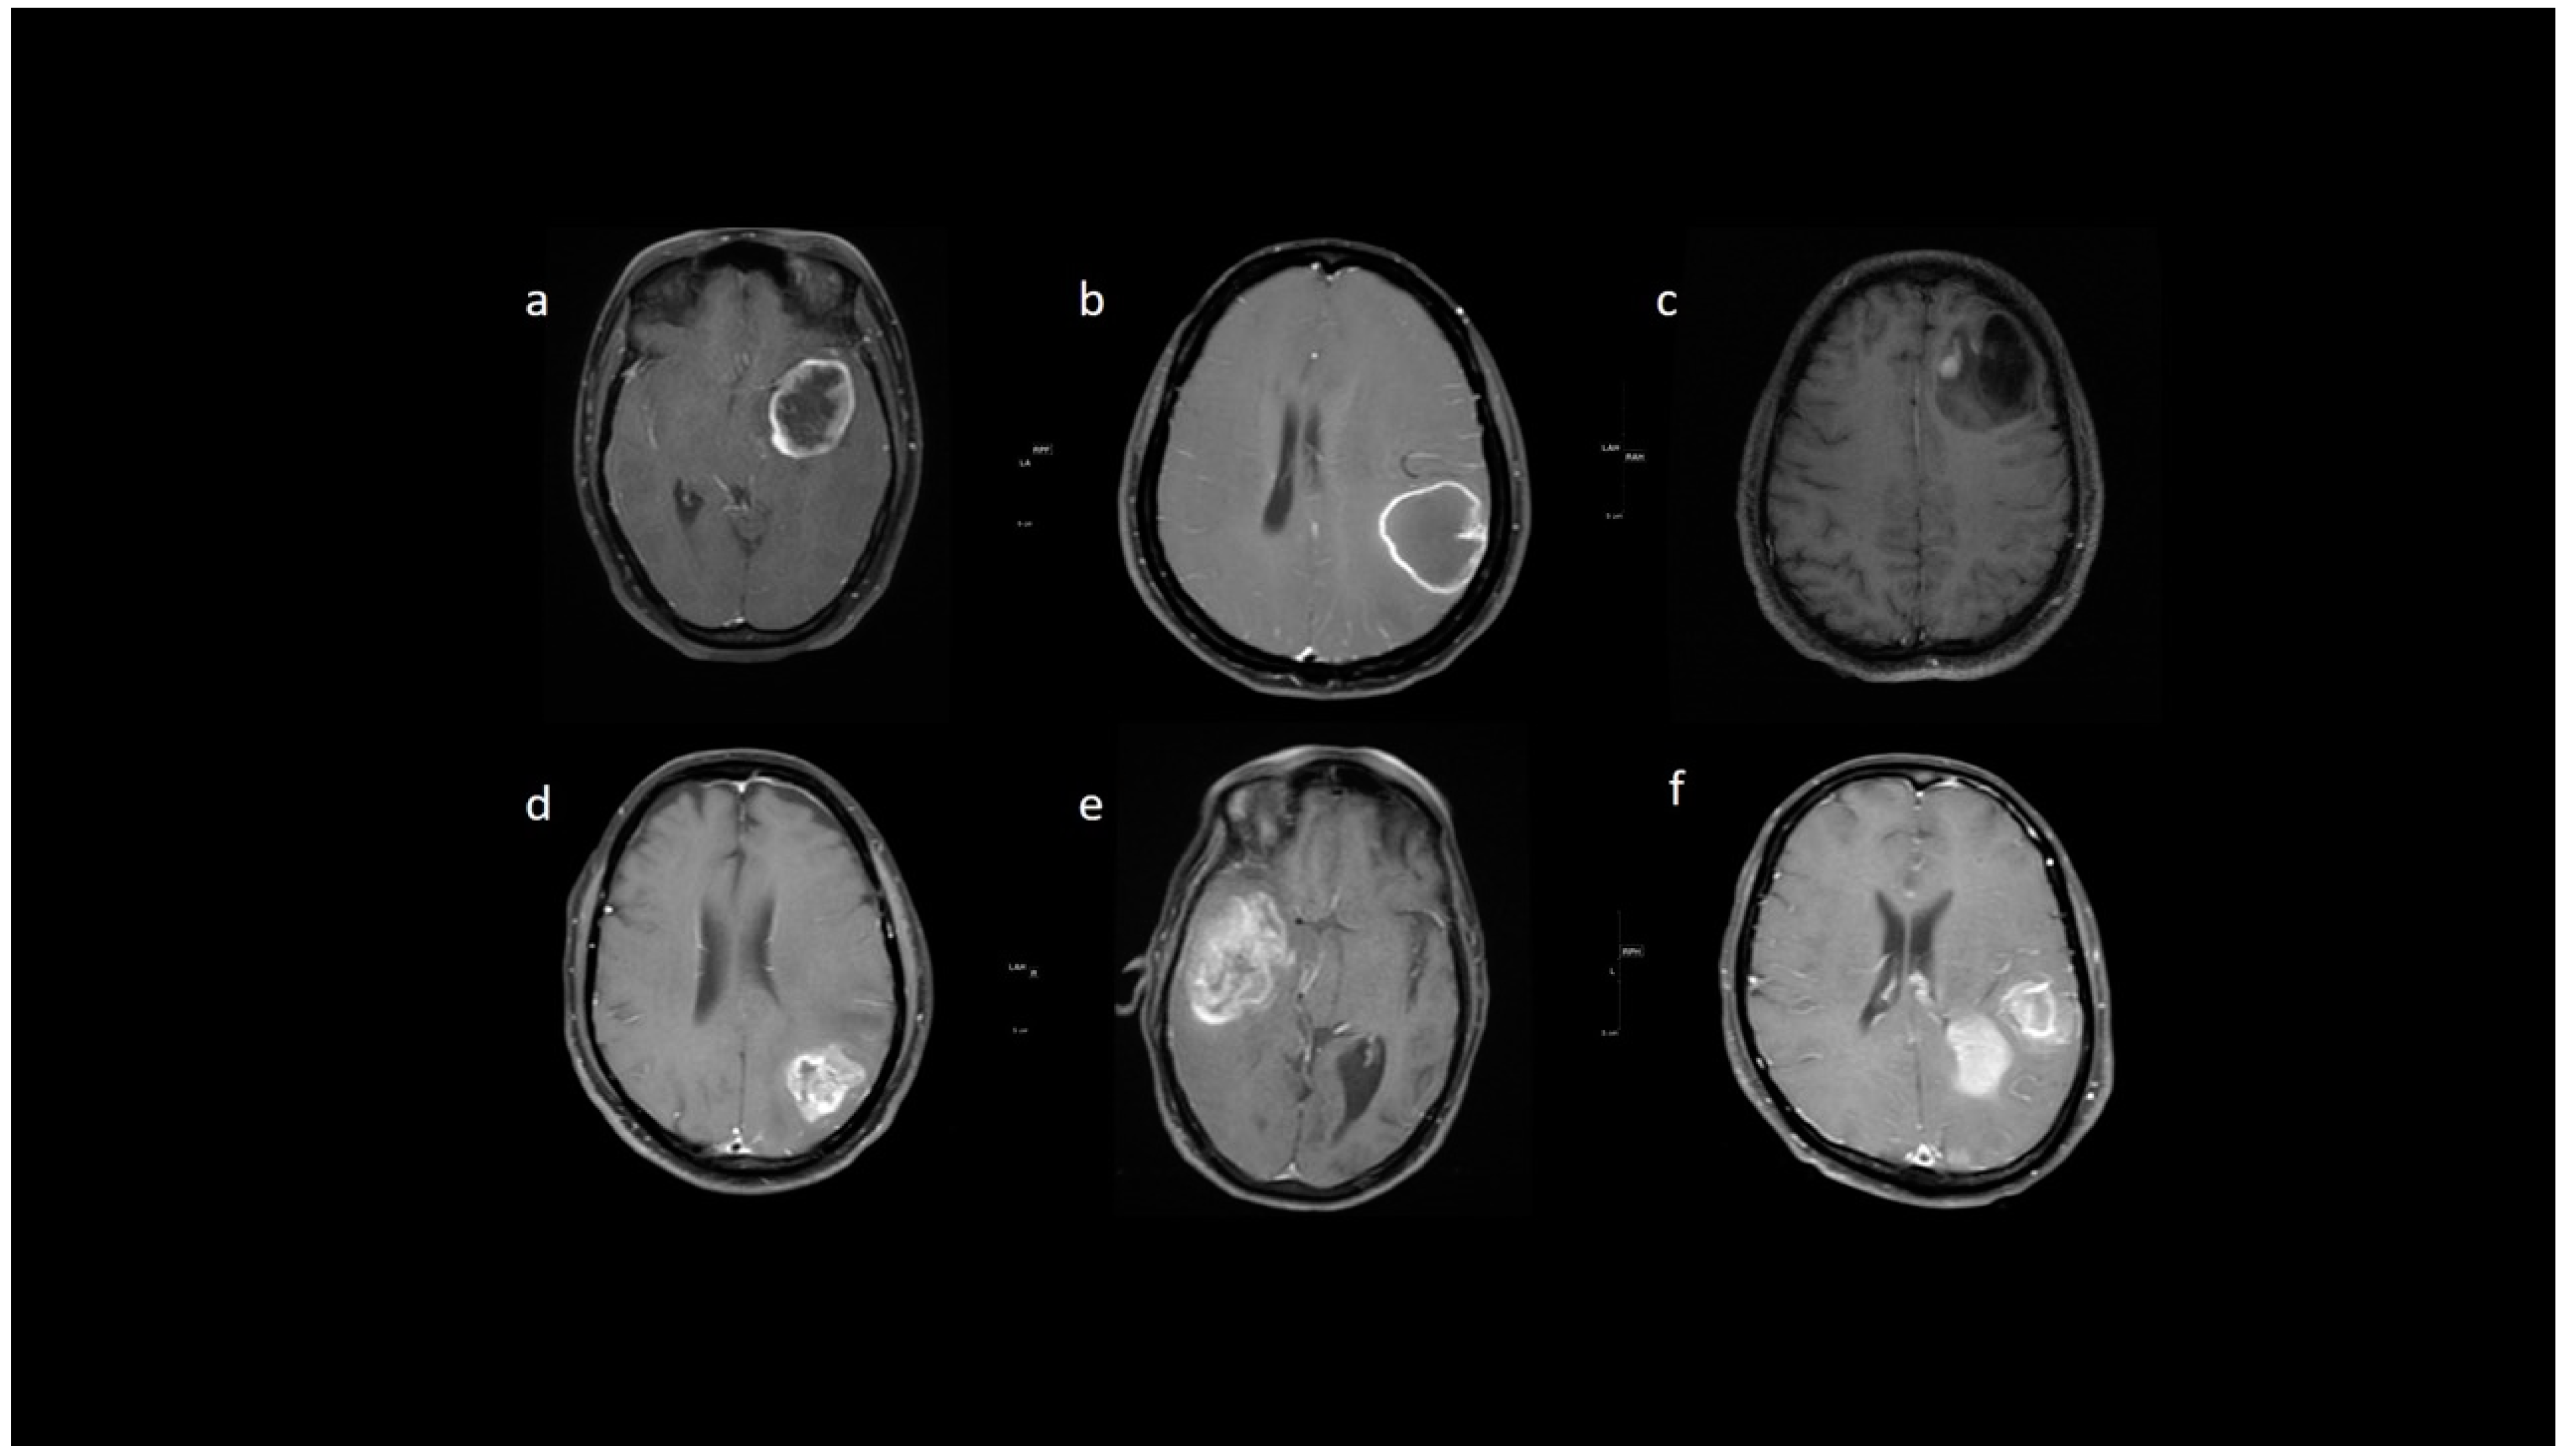

3.2. MRI Parameters of IDH-Wildtype vs. Mutant Phenotype Tumors

| Necrosis | None | 3 (15.8) | 3 (2.3) | <0.001 |

| <25% | 11 (57.9) | 14 (10.9) | ||

| 25- 50% | 2 (10.5) | 35 (27.1) | ||

| >50% | 3 (15.8) | 77 (59.7) | ||

| rCBV | Median (IQR) | 1.8 [1.4–2.0] | 2.6 [1.9–3.5] | 0.001 |